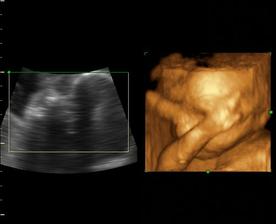

Od 19. júna 2008, teda od 21. týždňa vieme, že sa nám na 99% narodí dievčatko...na mene neodznela ešte úplná zhoda, preto Ema alebo Silvia...no ja dúfam, že sa mi podarí presadiť Emu, aj keď Silvia je tiež krásne meno...🙂...

a dnes, 16.10.2008, teda v 38. týždni, padlo definitívne rozhodnutie o mene...skôr moje rozhodnutie ako tatkove...🙂...takže naša prvorodená dcérka sa bude volať Ema Silvia...🙂